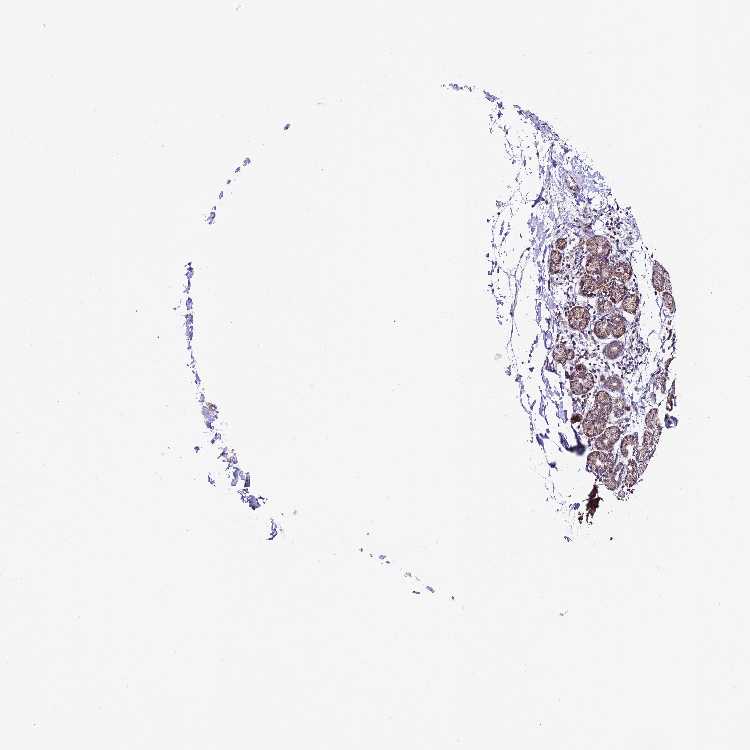

Antibody HPA044803

Glandular cells High